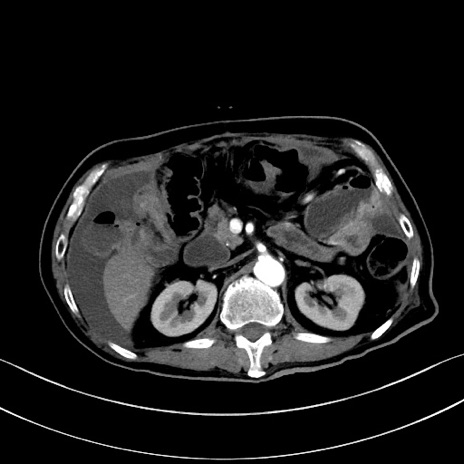

症例28(横断像)

【症例】60歳代男性

【主訴】嘔吐

【現病歴】胃癌にて胃全摘後。食思不振が悪化し、夜中に嘔吐することがある。

【既往歴】胃癌、胃全摘、脾摘、胆摘後

【データ】WBC 5900、CRP 10.56